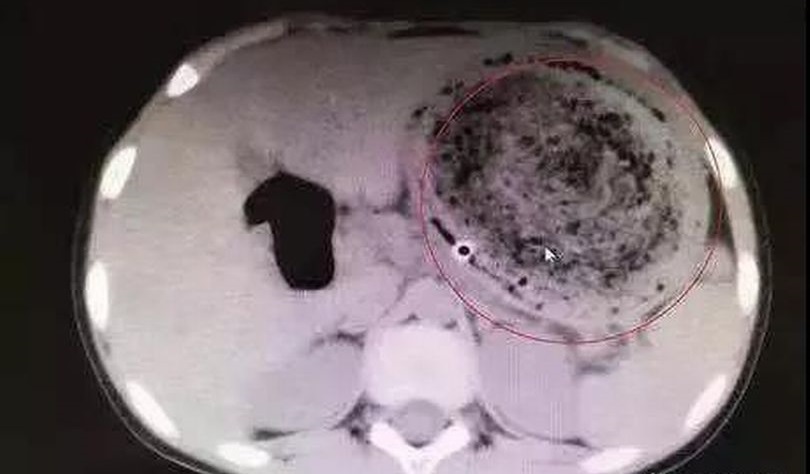

医師が少女の胃で発見したのは衝撃的なものでした。それは1.5㎏にもなる髪の毛の塊だったのです。

後で分かったことだが、少女は2歳の時から習慣的に髪の毛を抜いて食べてきたことが分かりました。子供たちにこのような異食症(pica)の症状はよく見られることで、親の厳格な注意が必要です。少女の母親は、少女は髪の毛を食べていることを知っていたが、大したことではないと思っていたといいます。

幸い手術後、少女は健康を取り戻しており、母親はこれからは娘が髪の毛を食べないようにきちんと見守ることを伝えました。